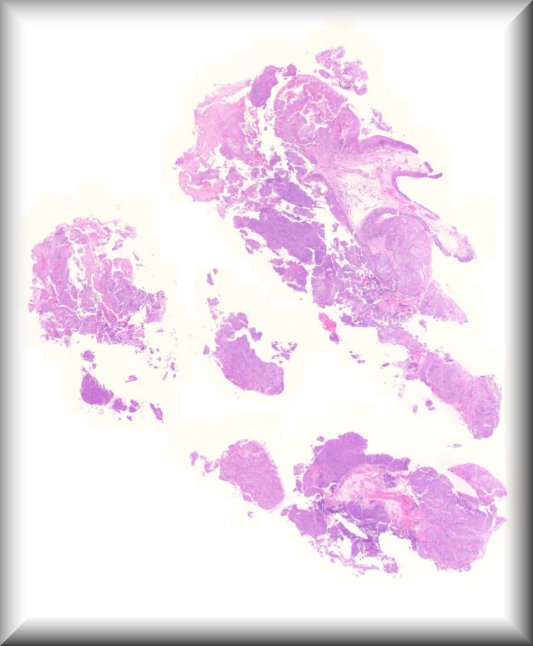

Alan D. Proia (Guest of Honor): A three-year-old boy developed proptosis over three weeks. Computed tomography and magnetic resonance imaging disclosed a 3.2 x 1.9 cm soft-tissue mass of the right extraconal and intraconal orbit with sphenoid bone erosion. The tumor was debulked through an upper eyelid crease incision. |